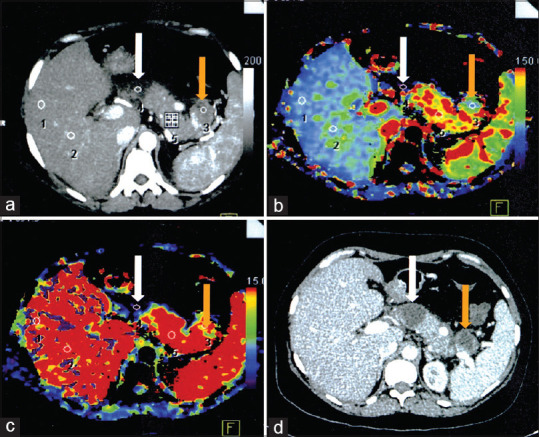

Methods: A prospective cross-sectional study was conducted on 50 SAP patients who underwent PCT within 72 h of symptom onset. PCT was performed to assess pancreatic blood flow (PBF), pancreatic blood volume (PBV), mean transit time, and time to peak. Follow-up contrast-enhanced CT was performed at 2 weeks to confirm necrosis. Perfusion parameters were compared between necrosis and non-necrosis groups. Diagnostic performance metrics (sensitivity, specificity, positive predictive value [PPV], and negative predictive value [NPV]) were calculated.

Results: Perfusion defects were identified in 21 patients, with 18 (85.7%) subsequently confirmed to have necrosis. The necrosis group had significantly lower PBF (35.49 ± 21.62 mL/100 mL/min) and PBV (11.16 ± 4.84 mL/100 mL) than the non-necrosis group (125.72 ± 50.37 and 17.67 ± 3.80, respectively, P < 0.05). PCT achieved 100% sensitivity, 90.6% specificity, 85.7% PPV, and 90.6% NPV. Optimal cutoff values were BF ≤57.87 and BV ≤14.90.